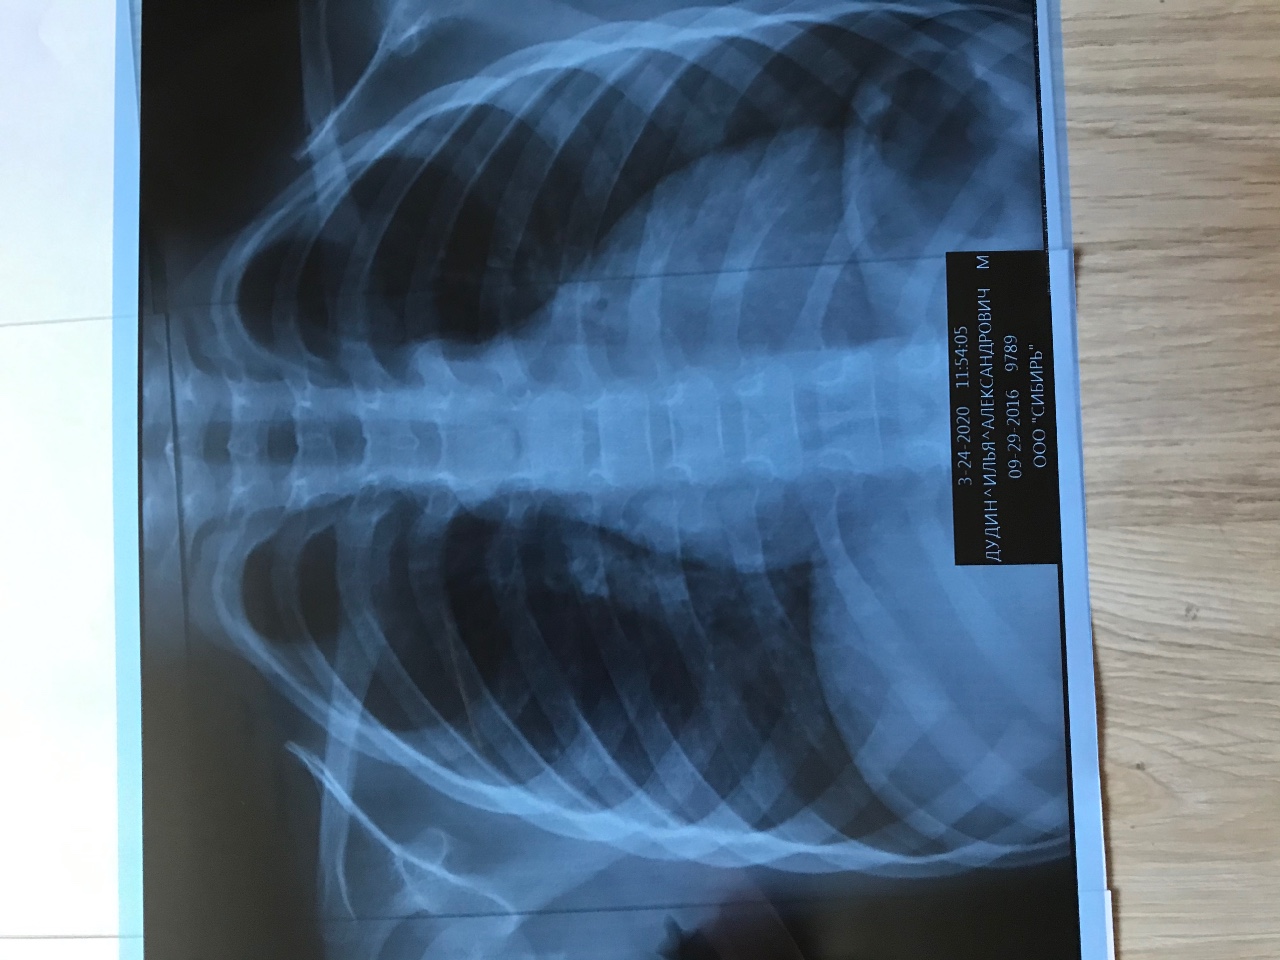

Рентгеновские технологии: усиленные экраны 35x35